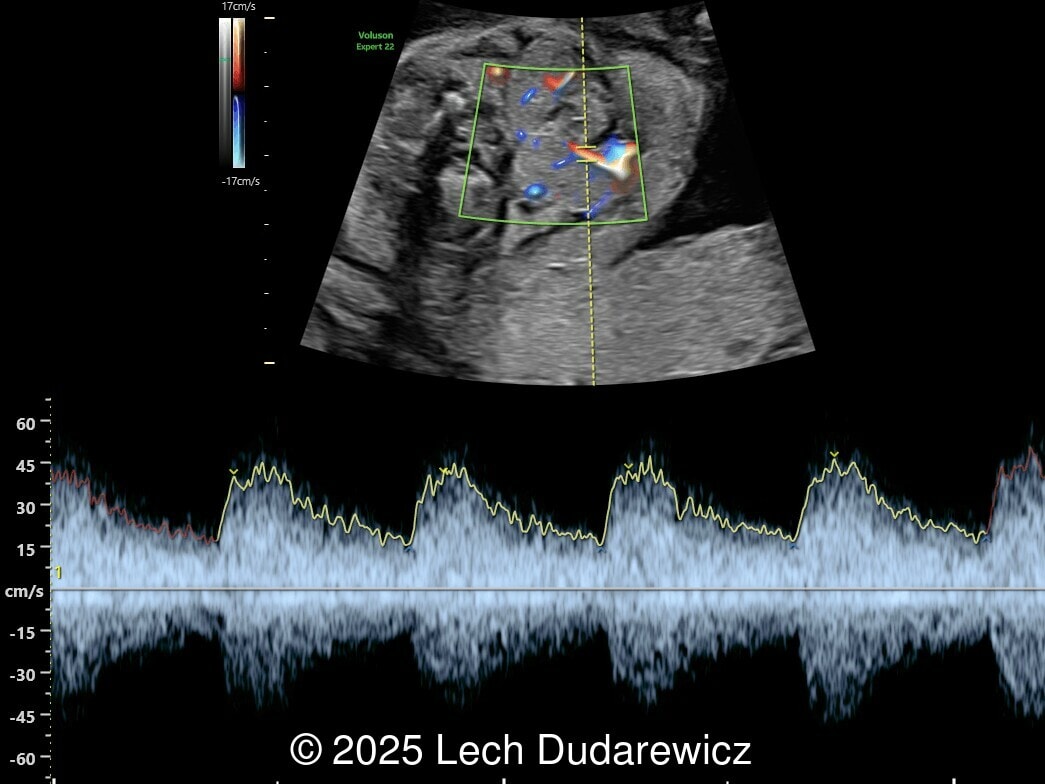

Image 1

Ultrasound images demonstrated a symmetrically enlarged thyroid gland that was isoechoic to slightly hyperechoic relative to the surrounding tissues. Color Doppler revealed peripheral hypervascularization of the thyroid, known as the “peripheral vascular rim sign”. No internal parenchymal hyperperfusion was noted. Amniotic fluid volume was within normal limits and no structural anomalies were observed in the remainder of the scan.

Prenatal ultrasound is the preferred method of screening for head and neck masses. The first ultrasound diagnosis of a fetal goiter was made by Weiner et al. in 1980 [11], and since then several cases have been published, mostly isolated or small series [12,13]. Ultrasound can accurately assess the size, location, internal blood supply, and growth of the fetal goiter, as well as evaluating its effects on neighboring structures and amniotic fluid volume. Key sonographic findings include a homogeneous, echogenic, symmetric mass in the anterior portion of the fetal neck corresponding to the thyroid enlargement (measurements above the 95th percentile for gestational age), polyhydramnios (not always present), and abnormal fetal neck contour [1]. On color Doppler evaluation, peripheral hyperperfusion ("peripheral vascular rim sign") supports the diagnosis of hypothyroidism with a hypertrophic but inactive thyroid gland. Diffuse parenchymal hyperperfusion (“thyroid inferno”), due to an overactive thyroid gland, is expected in hyperthyroidism [14,15]. Three-dimensional ultrasound may facilitate the parent’s understanding of the fetal goiter [16] and magnetic resonance imaging (MRI) can be useful for evaluating the compression and patency of the trachea and esophagus [17].